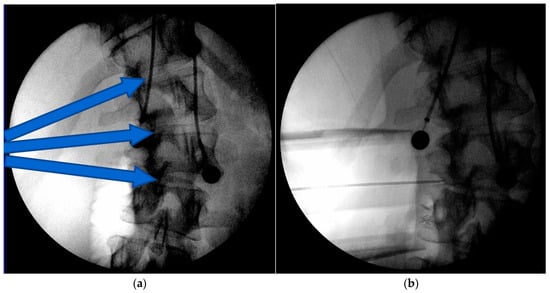

Figure 3.

Intraoperative images of the less invasive technique to the concave apex of the curve (a), The arrows indicate the planned trajectories and location for the wound incision. A radiographic marker is placed to confirm levels (b). Coronally tapered trials are used to determine interbody implant sizes starting at the end vertebral levels and working subsequently to the apical levels (c). The screw staple implants are then placed at the end vertebra first and then subsequently placed through the apical vertebral levels (d,e). Distraction is then applied between each segment and the rod secured to the transverse vertebral body screws (f).

The traditional surgical convex approach is well known for ASF (Figure 1). The concave surgical approach is not as well known and is briefly described (Figure 2). The anesthetized patient is positioned in a lateral decubitus position with the curve convexity down and the concavity up. The bed is flat during this portion of the procedure, yet the table’s flexion axis is at the apex of the patient’s curve to allow for subsequent table bending to assist in curve correction (below). After prepping and draping, imaging is obtained to plan the less invasive incision over the concave apex of the curve (Figure 3a). Because the spine is rotated away, the actual incision may be slightly anterior from the true lateral. In thin younger patients, one can use a minimally invasive approach using a 3-bladed minimally invasive retractor. The minimally invasive technique is used in 7/11 cases. A standard retroperitoneal approach is made. The wound may be deep and thus if the patient is large, a more extensive open approach will be needed. A radiographic marker is placed to confirm levels (Figure 3b), and the segmental vessels are ligated after approaching the lateral spine just anterior to the psoas. Psoas muscles are released from the antero-lateral aspect of the underlying discs and vertebral bodies and then retracted posteriorly. The most proximal disc and distal disc segments are then verified for access. Typically, the upper disc is approached first, most commonly just below the diaphragm. A large annulotomy and a generous discectomy is performed, the cartilaginous endplates removed, and the bony vertebral endplates prepared. A coronally tapered interbody device trial is used. After sizing, the transvertebral body screws (the author prefers mono type screws) and staples are placed transversely across the vertebral body parallel to the endplate and obtaining bicortical purchase. The OR table may be flexed as needed to facilitate the placement of the trials or screw/staple constructs. Subsequently, the distal disc level is approached, and typically, a combined coronally tapered and lordotic trial is used distally. This is repeated subsequently at the apical levels (Figure 3c). The screw staple implants are then placed at the end vertebra first and then subsequently placed through the apical vertebral levels (Figure 3d,e). Staples are used to prevent toggle of the screws, which are predominantly in cancellous vertebral body bone.